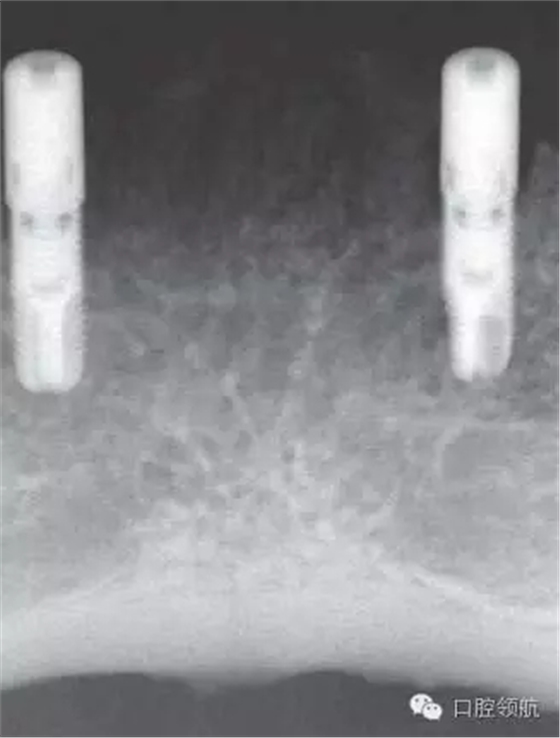

初診時(shí),口內(nèi)所見(jiàn)(圖1),曲面斷層片顯示(圖2),患者植入?yún)^(qū)骨量不足,前庭溝深度不足,附著齦的量不足。

圖2 初診時(shí)曲面斷層影像。